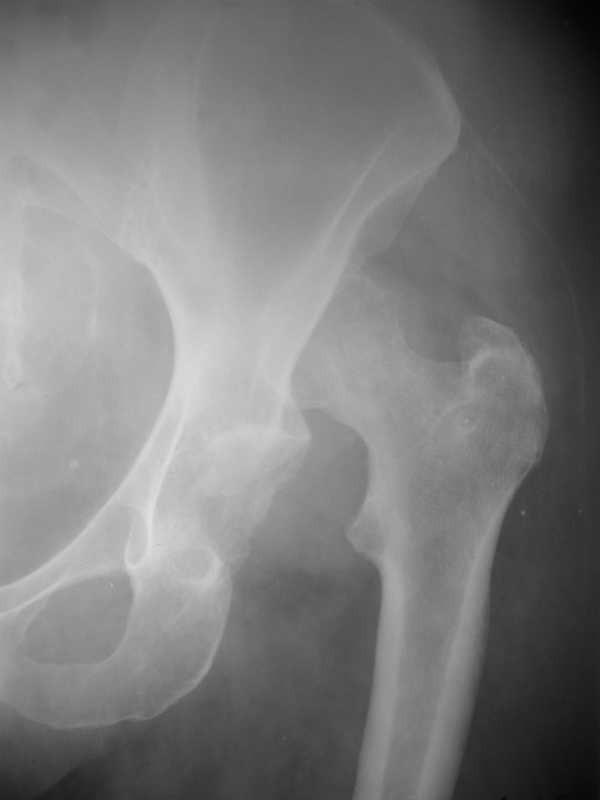

Застарелый вывих бедра

Уважаемые коллеги! Обратилась больная К. 57 л. Травма 1,5 года назад -упала на улице, обращалась в травмпункт.

Была отпущена домой с диагнозом ушиб левого тазобедренного сустава. Ходила с костылями. В данный момент жалобы на умеренные боли в левой нижней конечности, укорочение 6 см. Имеется контрактура левого тазобедренного сустава. Предлагается обсудить тактику лечения: начать с наложения дистракционного аппарата с постепенным низведением головки бедра и последующим эндопротезированием тазобедренного сустава.

Коллеги, как-то сказать с уверенностью что головке - хана! (некроз), по этим снимкам - ....сомнительно как-то, хотя....хотя, "все может быть".

низведение бедра в АВФ с последующим эндопротезированием, состояние головки бедра не имеет особого значения, скорее всего рассосется при любом виде операции, да и без нее.